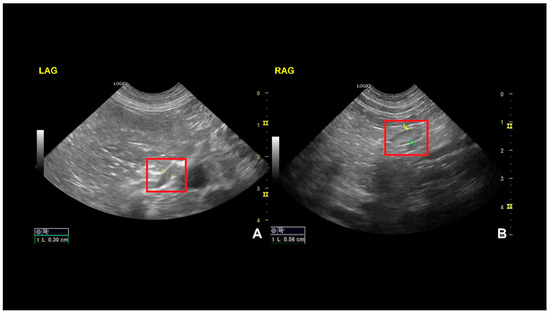

An abdominal ultrasound was performed using a General Electric LOGIQ V5 Expert Ultrasound Machine (GE Medical Systems, Wuxi, China) equipped with a 7.5–10 MHz microconvex transducer and a 7–13 MHz linear transducer. The examination was conducted in a counter-clockwise direction, starting with the urinary bladder. Abdominal ultrasonography was performed according to the American College of Veterinary Radiology and European College of Veterinary Diagnostic Imaging consensus statement for the standardization of abdominal ultrasound examinations [11]. Except for the thickness of the left adrenal gland, there were no other remarkable findings. The left adrenal gland was visualized according to the following anatomic landmarks: medial and cranial to the apical pole of the left kidney and ventro–lateral to the aorta between the cranial mesenteric and the left renal arteries [12]. Color Doppler was used to differentiate the organ in question from the adjacent vasculature and find the phrenicoabdominal vein. The left adrenal gland had a normal shape and echogenicity, with a diameter of 3 mm on the longitudinal axis at the caudal pole (normal values: 5.3–6.3 mm) (Figure 2) [13]. The right adrenal gland was visualized according to the following anatomic landmarks: craniomedial to the renal hilus, lateral or dorsolateral to the caudal vena cava, and cranial to the right renal vein [14]. The right adrenal was normal-shaped and exhibited echogenicity, with a diameter of 0.56 cm on the longitudinal axis at the caudal pole (normal values: 5.9–6.9 cm) [15].

Figure 2.

Adrenal gland ultrasound images of a dog, showing the longitudinal axis. On the left (A) is the left adrenal gland (LAG), with a diameter of 3 mm, corresponding to an ultrasound change consistent with HA; one the right (B) is the right adrenal gland (RAG), with a normal diameter of 5.6 mm.

There is a wide range of normal sizes for the adrenal gland in dogs depending on the breed. However, studies show that adrenal glands below 0.32 cm combined with clinical signs suggestive of primary hypoadrenocorticism are strongly suggestive of disease [21,22].

Among the landmarks that helped orient the diagnosis was the Na:K ratio of 15.5 upon presentation, since, as demonstrated before by Adler et al., a ratio of 24 or less makes the likelihood of hypoadrenocorticism very high [24]. A second highlight was the basal cortisol value, which was below 1 µg/dL. The research conducted by Lennon et al. showed that basal cortisol concentrations of ≤1 μg/dL had a sensitivity of 100% and a specificity of 98.2% for detecting dogs with hypoadrenocorticism [9]. On the other hand, Bovens et al. recorded a sensitivity of 85.7% for basal serum cortisol concentration ≤ 1 µg/dL and a specificity of 91.8% for detecting hypoadrenocorticism [25], which underlines that a definitive diagnosis of hypoadrenocorticism should only be made after an ACTH stimulation test. Also, the ultrasound evaluation of the adrenal gland revealed a remarkably reduced size compared to values reported in the literature for healthy dogs in the same weight category [13,26].